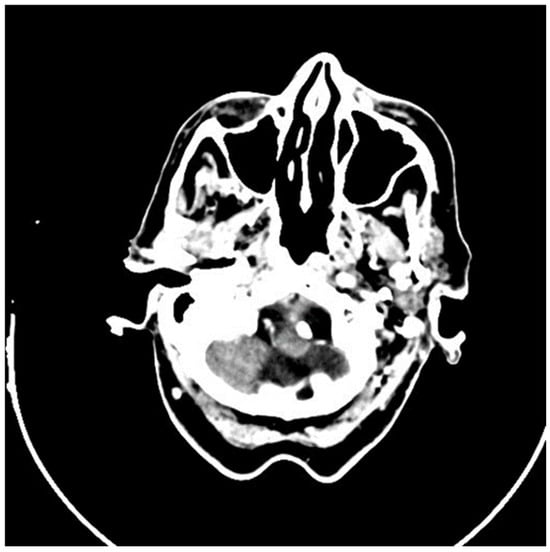

2.2. Imaging and Preoperative Diagnostics